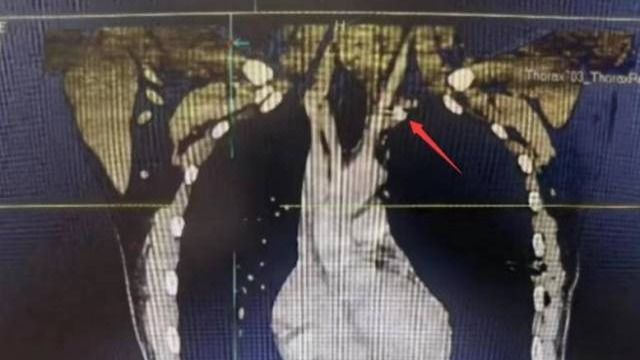

【南方日报】中大五院全力急救被金属异物刺穿颈部动脉患者

近日,中大五院胸外科成功为一名“熊猫”血型(B型Rh阴性)的左颈动脉外伤合并气胸的患者实施手术,取出一枚嵌插于左颈总动脉根部的金属异物,并修复了患者血管破口,避免大出血。原来,23岁的徐先生被高速旋转的金属模具碎片射中左侧颈根部,当即出现疼痛、呼吸困难,被紧急送到中大五院治疗。据医院外科主任兼胸外科主...